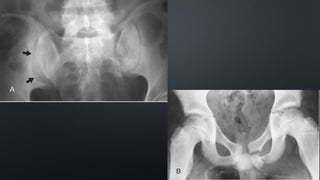

1.Bilateral superior and

right-sided inferior

pubic rami fractures

(black arrows)

2. A subtle disruption of

a right sacral arcuate

line (white arrow).

1.Left-sided overlapping

superior and inferior pubic

rami fractures (white

arrows)

2.Widening of the left SI

joint (black arrow).